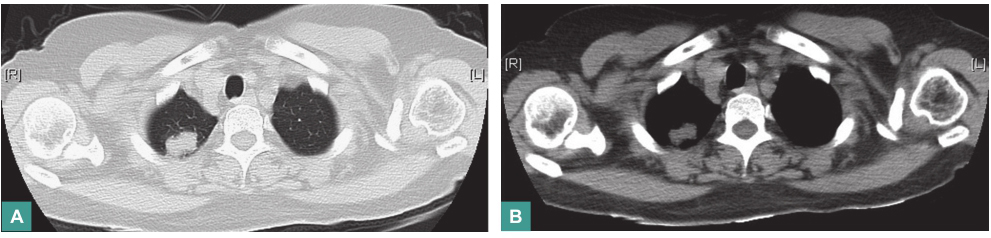

胸部CT(2016年2月3日):

右肺上叶尖段椭圆形密度增浓影,边界较清楚,呈浅分叶状,大小为1.3cm×2.1cm(图1)。

图1 胸部CT表现